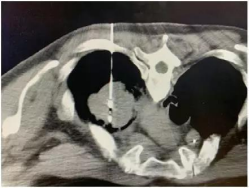

经CT检查发现肿瘤血运非常丰富易出血。所以复大的医生先给他做了一个穿刺活检,明确肿瘤的性质。

牛立志教授用2.0的微波针,穿刺到肿瘤中心,十分钟就将肿瘤消融掉了。消融后,可以看到肿瘤被烧死,同时看到毛玻璃样改变。

整个过程,病人没有任何出血发生,术后也没有咳血,全程“零出血”。这也证明了采用微波消融是一个正确的选择。